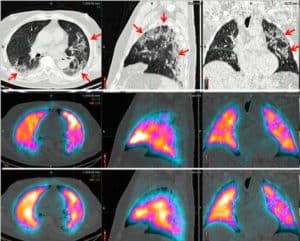

Detectorii digitali care captează un număr maxim de fotoni oferă imagini 3D detaliate, superioare tehnologiei planare Anger. Sistemul SPECT/CT multifuncțional permite scanări complete cap–picioare într-o singură sesiune, oferind informații precise și reducând disconfortul pacientului.

- Workflow-ul SPECT/CT total-body cu acoperire continuă de 2 m oferă eficiență superioară și informații detaliate față de scanările planare tradiționale. Imaginile 3D corectate pentru dispersie, atenuare și volum parțial pot genera, la nevoie, vizualizări multi-view planare (MVP).

- Îmbunătățirea detecției leziunilor este doar începutul. O singură scanare completă oferă imagini 3D de tip PET, reducând timpul de examinare și permițând utilizarea unei doze mai mici, optimizând modul de desfășurare al investigațiilor imagistice.

V/Q Scan cu Technegas